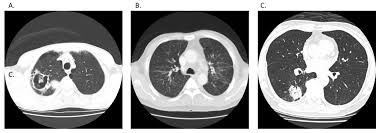

Can Lung Cancer Be Mistaken For Tuberculosis / Cancer And Tb / Since mycobacterium tuberculosis (mtb) is an intracellular organism, bacterial dna could integrate to bronchial epithelial cells inducing neoplastic transformation.. Primary tuberculosis usually begins in childhood and affects the lungs and bronchial lymphatic glands of the lung roots. Tuberculosis (tb) is a contagious infection that usually attacks your lungs. The occurrence of pulmonary tuberculosis (ptb) and lung cancer as comorbidities has been extensively discussed in many studies. Most lung cancers do not cause any symptoms until they have spread, but some people with early lung cancer do have symptoms. Pulmonary tuberculosis is caused by mycobacterium tuberculosis, which produces characteristic tuberculosis changes in the lung.

Tuberculosis, a disease that used to be common in the uk and other western countries, was thought to have been successfully controlled when vaccination was introduced. Interestingly so, tuberculosis has been known to mimic lung cancer due to its presentation in the form of pulmonary infiltrates and mediastinal lymphadenopathy however, in the reported cases where pulmonary tuberculosis was mistaken for pulmonary malignancy, a number of different, costly. Iteither enlargesas disease progresses or, much. Lung can suggest early symptom of tuberculosis). You can't get it from shaking hands with someone who has it or by sharing their food or drink.

Difference between lung cancer and tuberculosis. This growth can spread beyond the lung by the process of metastasis into nearby tissue or other parts of the body. Selection of the most suitable tests for detection of m. However, this can also occur with tuberculosis or a pulmonary embolism. Concomitant active tuberculosis in nsclc (tblc) resembles locoregional immunotherapy of tumor cell vaccine; Primary tuberculosis clinical forms the primary site of infection in the lungs is called the ghon focus. Living with advanced breast cancer. Symptoms of tuberculosis and lung cancer are overlapping and it is difficult to differentiate without the histopathological report. When people with lung tb cough, sneeze or spit, they propel the tb germs into the air. Lung cancer and pulmonary tuberculosis (tb) comorbidity is a clinical problem that presents a challenge for the diagnosis and treatment of both diseases.objective: Tuberculosis (tb) is a potentially serious infectious disease that mainly affects the lungs. Primary tuberculosis usually begins in childhood and affects the lungs and bronchial lymphatic glands of the lung roots. You can't get it from shaking hands with someone who has it or by sharing their food or drink.

Interestingly so, tuberculosis has been known to mimic lung cancer due to its presentation in the form of pulmonary infiltrates and mediastinal lymphadenopathy however, in the reported cases where pulmonary tuberculosis was mistaken for pulmonary malignancy, a number of different, costly.